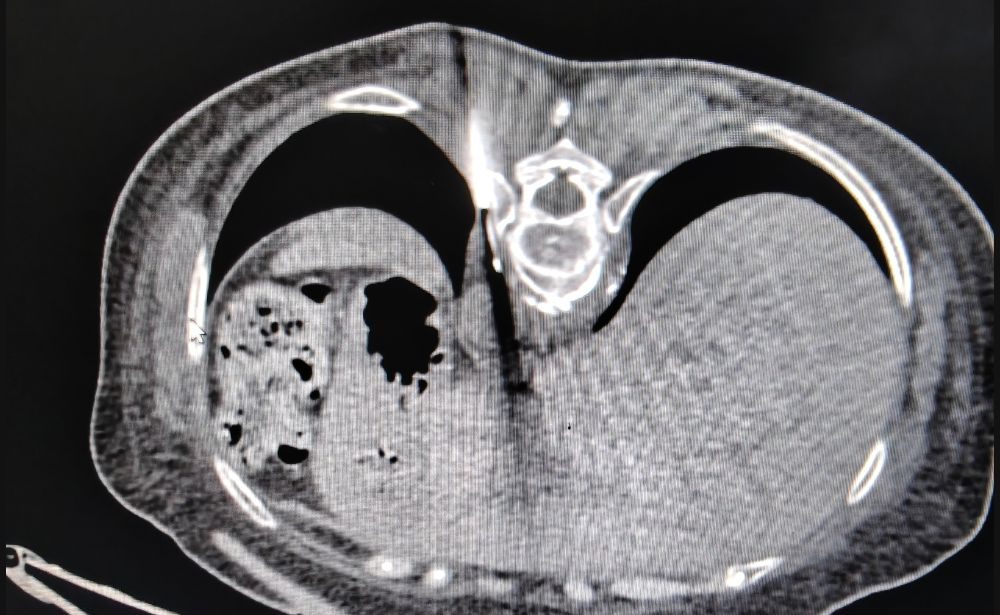

What it is: A procedure to drain unwanted fluid or pus (an abscess) from inside your body. A thin, flexible tube called a “pigtail catheter” is placed into the collection using imaging guidance.

How it helps: Relieves pain and pressure, treats or prevents infection, and allows the affected area to heal. It is a life-saving procedure for deep-seated infections.

Commonly used for: Draining abscesses in the liver, abdomen, or pelvis, and managing post-surgical fluid collections.